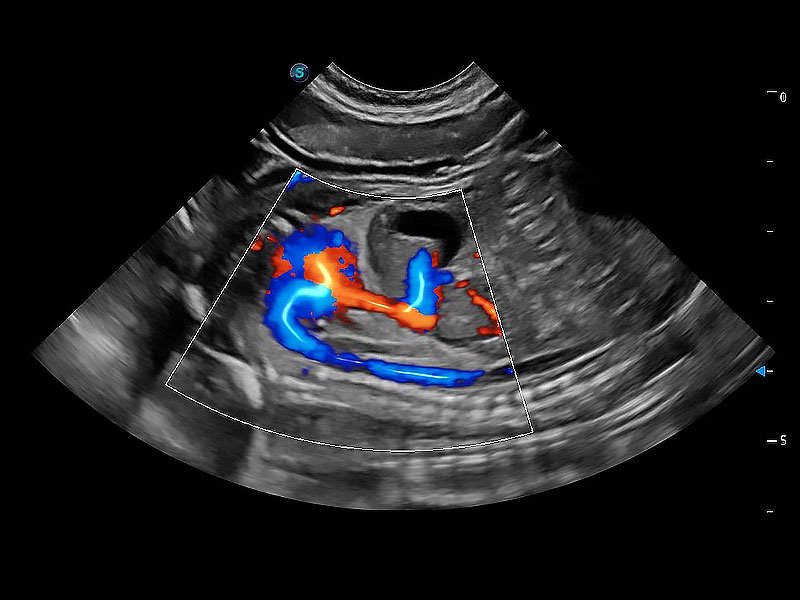

(犬)二腔心血流